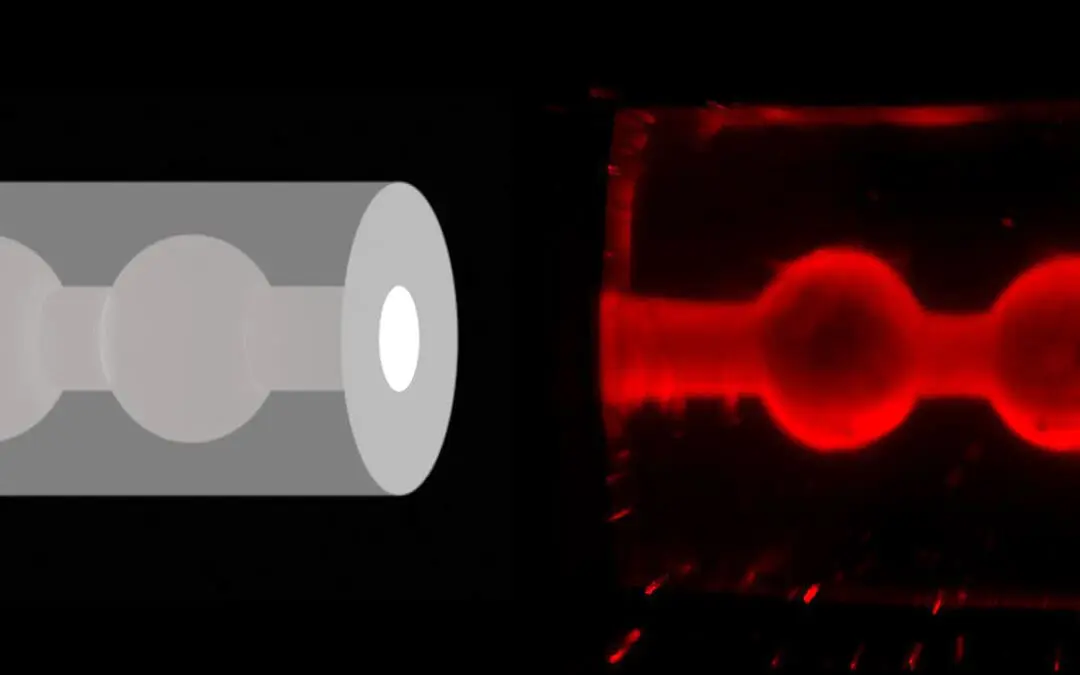

Cells with mechanical memory: New insights into cell movement

Researchers at the University of Basel and the University of Mons in Belgium have discovered that migrating cells have a mechanical memory that helps them move more efficiently through narrow tissue structures. This finding, published in the journal Nature Physics,...